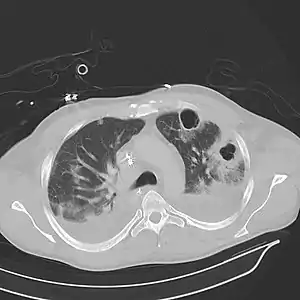

Abces pulmonar

Abcesul pulmonar este o colecție la nivelul parenchimului pulmonar, netuberculoasă, circumscrisă. Acesta este caracterizat de prezența de spații cavitare pline cu puroi. În cazul unor acumulări purulente numeroase (mai mici de 2 cm) se vorbește de pneumonie necrozantă.[4]